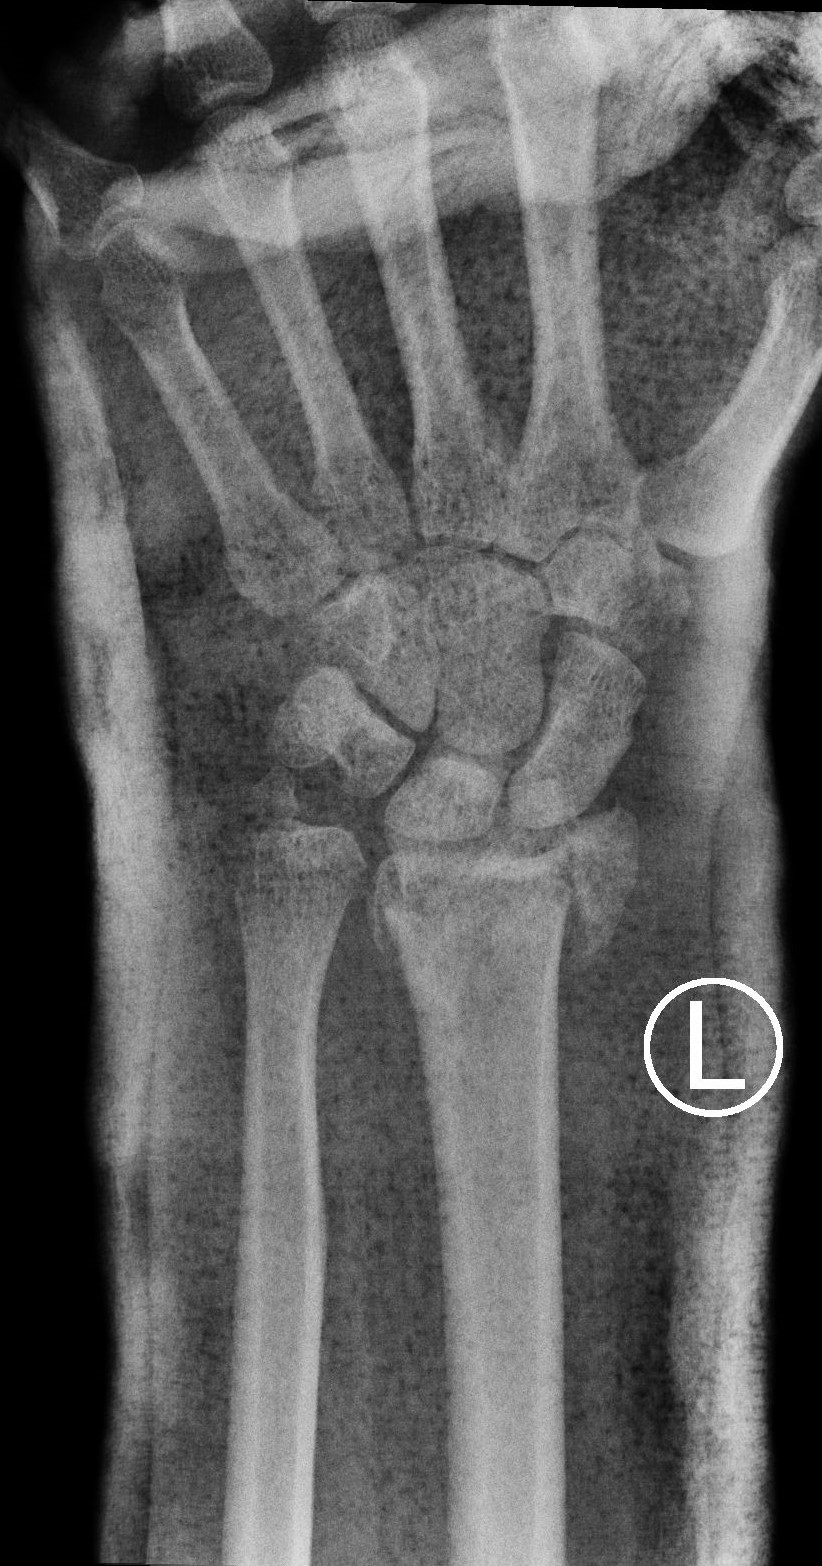

Treatment of neglected, displaced or united distal radial fractures (DRFs) is difficult, because it requires either wedging the almost consolidated fracture and reduction to the correct position, or cutting the united bone and putting it in the correct position (corrective osteotomy). Both treatments are associated with the risk of failure and complications. The paper presents a case of almost fully united DRF in a man, in whom 5 weeks after the injury, and after unsuccessful primary fixation with K-wires, the bone fragments were surgically wedged, aligned and fixed with a palmar plate. The result of treatment after 2 months was satisfactory. Early surgery allowed for a significant shortening of the recovery period and allowed the patient to return to work.